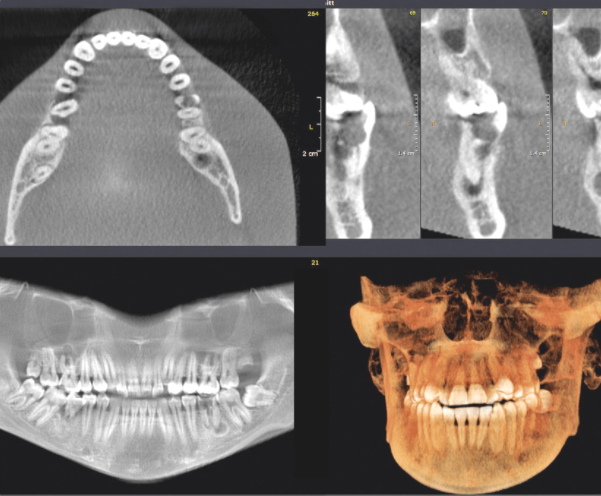

При тотальной реабилитации полости рта есть определенные этапы. Начинаем мы всегда с диагностики. То есть это функциональная диагностика, туда входит фото протокол, модели, электронная аксиография, анализ окклюзии в артикуляторе, может быть МРТ височно-нижнечелюстного состава, может быть компьютерная томография всех зубов, верхней нижней челюсти. После этой диагностики, если мы выявили проблемы с суставом или с окклюзией, мы можем изготовить сплинт, но опять же это делается по показаниям, если у пациента есть эти проблемы. Когда мы разобрались с окклюзией, убрали боль в суставе, боль в мышцах, мы проводим лечение или как раньше говорили – санацию полости рта. То есть мы лечим весь кариес, мы лечим осложнения кариеса, у кого-то может быть раньше были депульпурованные зубы и из нужно перелечить или во всяком случае сделать ревизию. Нужно вылечить десну, привести в порядок, чтобы она была здоровая. Когда мы сделали санацию, у кого нет зубов, нужно установить имплантаты, у кого сильно разрушены зубы или корни их нужно удалить и тогда сделать имплантацию. Когда вот это все мы подготовили, мы делаем восковое моделирование оно как правило делается по одной из двух методик. Первая – делать воск вручную, вторая – моделировать в программе, так называемое цифровое моделирование. После этого мы согласовываем с пациентом будущую форму зубов, можем сделать пробную реставрацию, чтобы он убедился, что эта форма ему подходит, а после этого уже мы обрабатываем зубы, снимаем оттиски и делаем временные реставрации как раз по форме будущих зубов. Эти реставрации делаются из фрезерованной пластмассы, которая называется полиметилметакрилат. Она достаточно прочная для того, чтобы ходить несколько месяцев с ней, но недостаточно прочная для того, чтобы с ней ходить постоянно. И вот когда пациент посмотрел, какая форма, где будут располагаться зубы, какой примерно будет цвет. После этого мы уже переводим прототип этих зубов. После того, как пациент пожевал, поговорил, попробовал их. То есть провел «тест драйв» зубами мы переводим его уже в постоянные реставрации. Постоянные реставрации как правило уже из керамики. Это особо прочные виды керамики такие как: оксид циркония, можем сделать имакс, можем из полевошпатной керамики сделать. Зависит от показаний, и что мы делаем. После того, как мы закончим лечение мы еще пациента постоянно ведем, раз в полгода приглашаем на профессиональную гигиену и на коррекцию окклюзии, чтобы эта работа служила у него долго. Как правило после тотальной реабилитации полости рта наши пациенты ходят от 10 до 25 лет. Можно сказать средний срок службы реставрации это примерно 15-20 лет.

Гнатологическая диагностика – это комплекс мероприятий, который направлен на то, чтобы выявить какие есть проблемы у пациента. В этот комплекс входит беседа с пациентом, опрос, входит пальпация мышц, пальпация височно-нижнечелюстного сустава, фото протокол, то есть фотографии лица с разных ракурсов, фотографии зубов для того, чтобы пациент увидел в каком состоянии зубы, чтобы мы увидели, что с зубами. Далее мы делаем оклюзограмму – это такой тонкий воск, который вставляется между зубов, пациент смыкает, и мы видим по отпечаткам на зубах, какие зубы соприкасаются, какие нет. Это именно для оценки именно соприкосновения зубов, для оценки окклюзии. Далее мы делаем оттиски, ставим гипсовые либо цифровые модели и делаем еще бруксчекеры. Бруксчекеры – это такие тоненькие пластинки, окрашенные пищевым красителем, которые мы выдаем пациенту. Он надевает их на зубы и 2 ночи проводит с этими бруксчекерами, потом мы смотрим, стискивает ли он зубы ночью, а если стискивает, то на каких зубах, какие есть движения и так далее. Еще одно посещение мы посвящаем тому, чтобы исследовать, как движется нижняя челюсть, то есть какие функции нарушены или что-то не в норме. Для этого мы надеваем электронный конделограф на голову пациента, прикрепляем к нижним зубам специальные датчики, пациент двигает, и мы получаем графики движения нижней челюсти, анализируем состояние височно-нижнечелюстного сустава, также мы делаем боковой снимок головы и проводим на этом снимке циклометрический анализ.